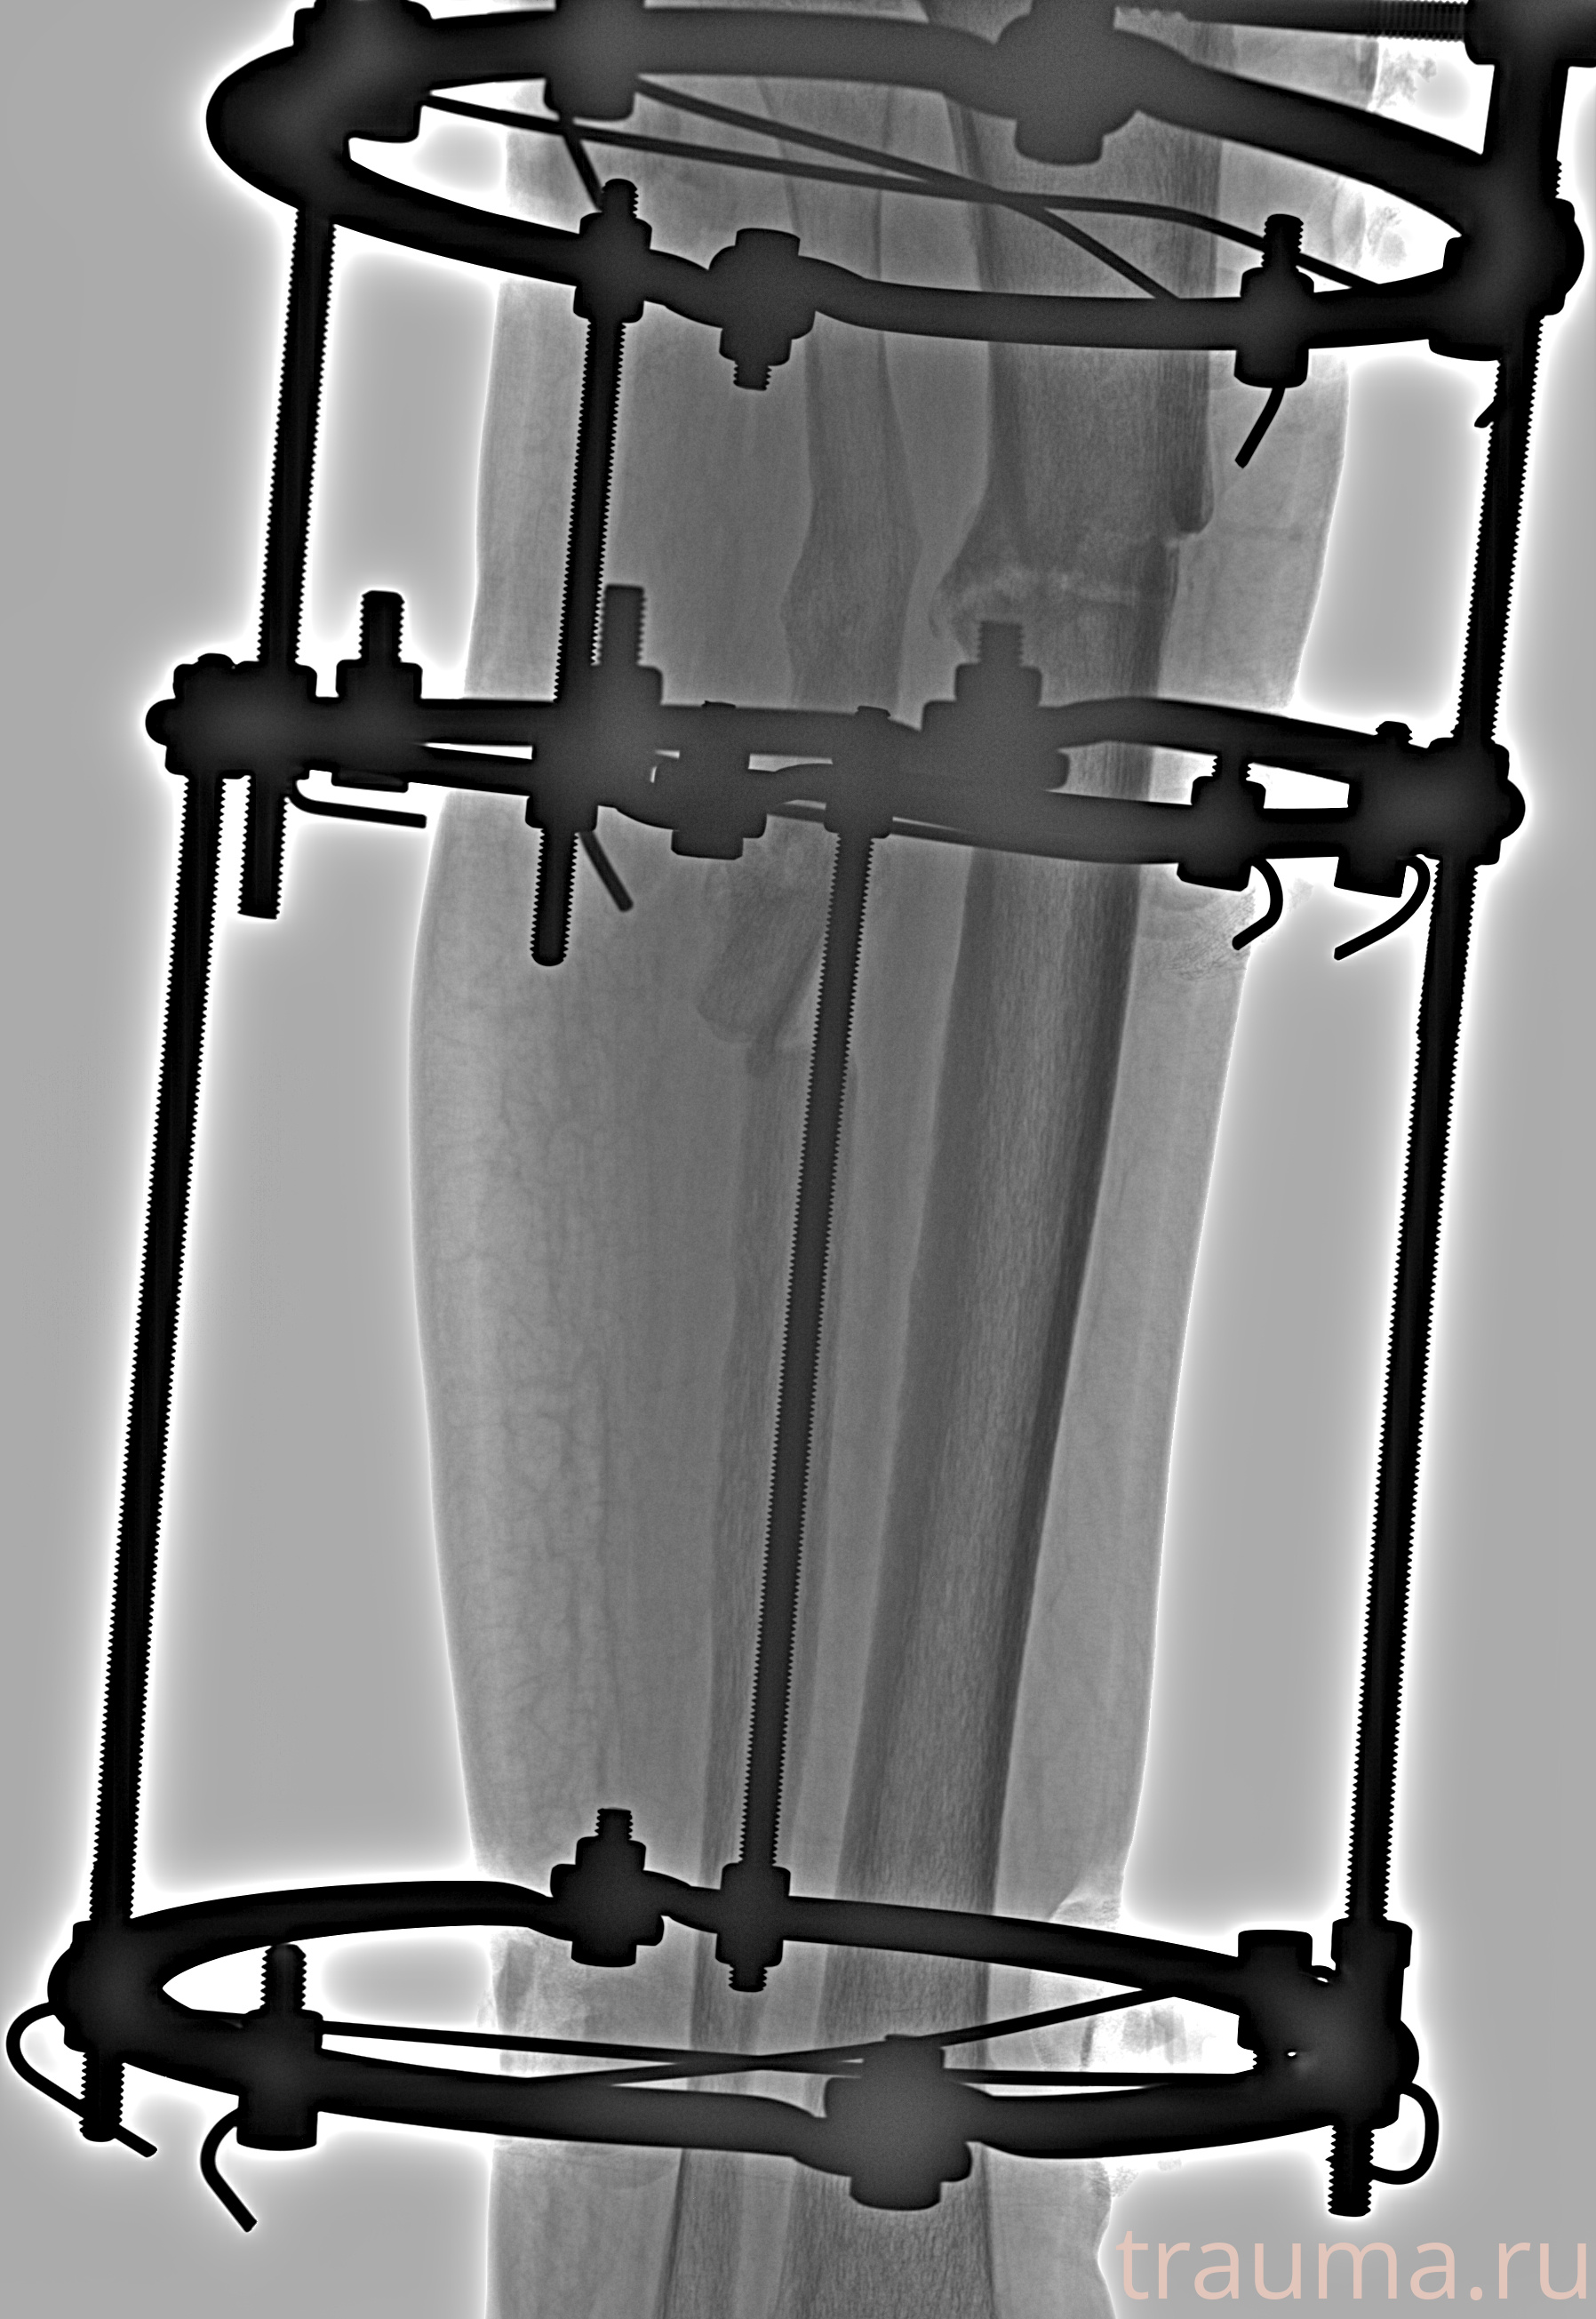

Рентгенограммы

Рентген на дому: по вашему адресу приезжает врач-рентгенолог, травматолог-ортопед с мобильным рентгеновским аппаратом, проводит диагностику травмы или заболевания, делает необходимые рентгенограммы, дает рекомендации по дальнейшему лечению. Получить качественные снимки в домашних условиях возможно благодаря уникальной методике, разработанной МосРентген Центром для института  Склифосовского